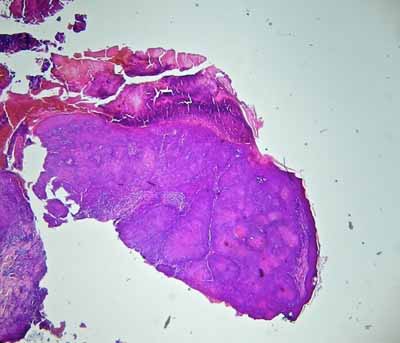

Les calques cutanés réalisés après retrait des croutes révèlent une réaction inflammatoire non spécifique avec surinfection bactérienne. L’analyse histopathologique de deux biopsies de la truffe, réalisée par Frédérique DEGORCE du LAPVSO, montre un épiderme hyperplasique et hyperkératosique recouvert d’un magma crouteux séro-cellulaire, à partir duquel prolifèrent des cordons épithélieux anastomosés et ramifiés, formant une prolifération épithéliale à localisation dermique associée à une stroma-réaction inflammatoire marquée. Les cordons cellulaires montrent un agencement pavimenteux et plan de cellules épithéliales polyédriques unies par des ponts épineux, avec kératinisation individuelle et collective (globes cornés). L’activité mitotique, l’anisocaryose et les atypies cyto-nucléaires sont faibles. Aucune image d’embolisation ni d’effraction vasculaire n’est constatée (photos 4, 5 et 6). L’analyse virale par PCR de prélèvements de truffe est négative.

Photo 4 : Observation microscopique (x40) d’une biopsie de la truffe.

Noter l’épiderme hyperkératosique recouvert d’une séro-croute,

et la formation épithéliale proliférante dans le derme.